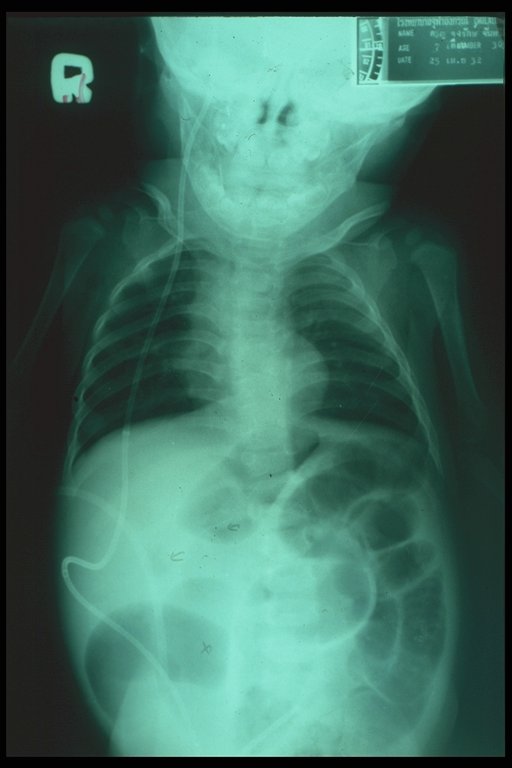

Plain abdominal X-ray in a hydrocephalous child demonstrates the picture of small bowel obstruction caused by the ventriculo-peritoneal (VP) shunt